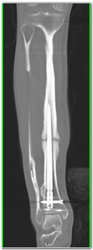

Diagnosis

Unusual Shaped Shield Sternum